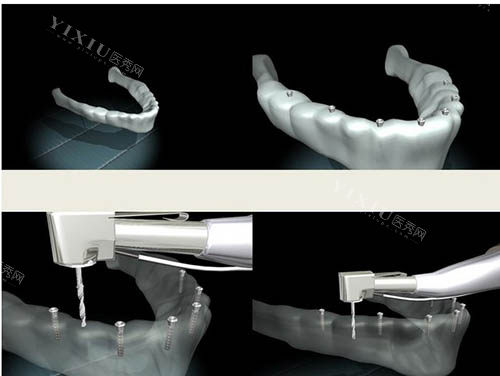

了解设备:

正规机构应配备CBCT、智能化导板设计软件等设备,确保手术精度。